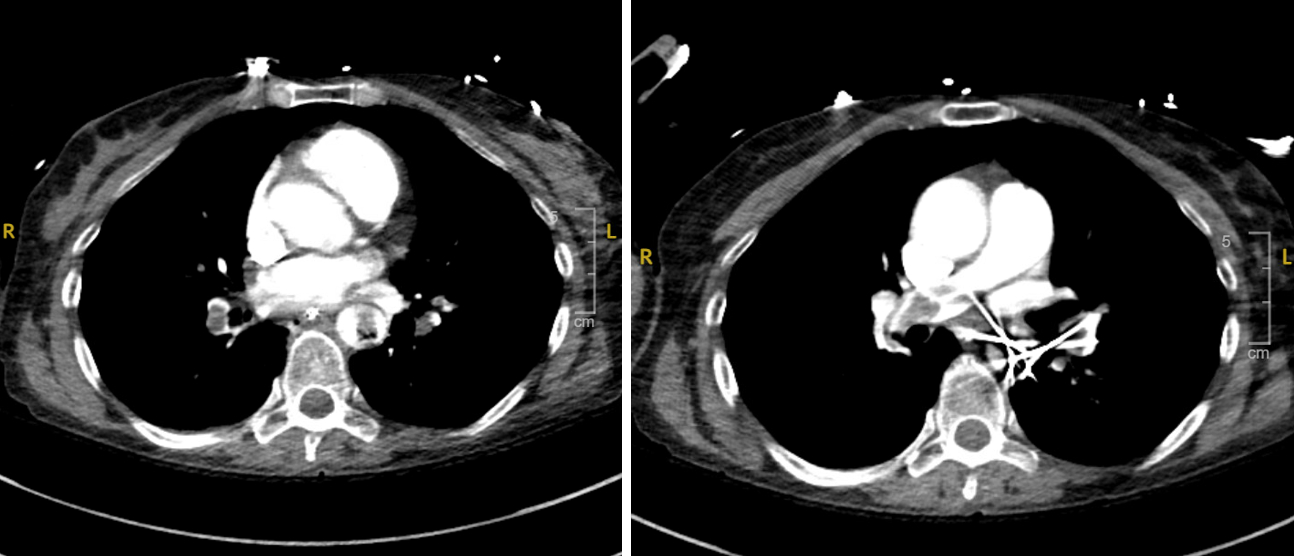

Abstract Body (Do not enter title and authors here): Case Presentation: A 53-year-old woman with a history of recent left patellar fracture and tobacco use presented with sudden-onset chest pain and shortness of breath. ECG showed ST elevations in II, III, and aVF with reciprocal depressions. CT angiography revealed a saddle pulmonary embolism with extensive bilateral emboli and right heart strain. Emergent coronary angiography showed 100% RCA occlusion - from proximal PDA through the AV groove. She was diagnosed with massive, high-risk PE and experienced progression from second- to third-degree AV block, which resolved after revascularization. Percutaneous coronary intervention was performed with successful RCA thrombectomy. She developed cardiogenic shock requiring norepinephrine and milrinone. The shock team placed an intra-aortic balloon pump (IABP). Ultrasound showed a non-occlusive thrombus in the left posterior tibial vein. Transthoracic echocardiogram on the following day of hospitalization showed normal LVEF (60–65%), RV dilation, septal flattening, and severely reduced RV systolic function. A bubble study confirmed a patent foramen ovale with right-to-left shunting. Due to RV wall thinning and elevated pulmonary pressures, the Pulmonary Embolism Response Team recommended IR-guided mechanical thrombectomy. Post-procedure, the patient improved and was weaned off IABP, pressors, and ventilator support. At discharge, she was started on a direct oral anticoagulant. One-month follow-up TTE revealed normalized RV size, mild right atrial dilation, and preserved LVEF.